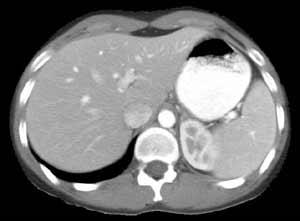

In CT, the absorption of the tissue is recorded as the X-ray source and a one-dimensional array of detectors are rotated around the patient’s body, resulting in a number of one-dimensional projections recorded at different orientations of the body (called sinograms).

In CT, the X-rays are collimated so that only a thin slice of the patient is probed during each acquisition. Image reconstruction can then be performed to create a cross-sectional image, where each pixel of the image represents the absorption of a given region of the crosssection. This whole procedure can then be repeated at different slice positions to build up a 3D volumetric model of the patient. Common applications of CT include investigations in staging of various tumours, calcifi cation, lung cancer, cerebral infarction, haemorrhage and abscesses, complex fractures, pulmonary diseases such as emboli and detection of acute and chronic pancreatitis.

Figure 13 lists the HU for verious tissue types. Notices that most of the soft-tissues, such as kidney and liver, have very similiar HU values. You should ask yourself why! That is to say, CT has very low image contrast for soft-tissues and thus one may not be able to differentiate soft-tissues of different types from CT easily.

The in-plane resolution of a CT image can be quite high, limited by the number of detectors. The out-of-plane resolution, i.e. the axial resolution, could be lower than that of the in-plane resolution, limited by the amount of translation of the translation used to move the object relative to the X-ray source and detectors. Modern CT scanners use in clinical setting are capable to achieve a resolution of or better.

Figure 15:CT scan of a liver, Image courtesy of Prof. Terry M. Peters at Robarts Research Institute, Canada.